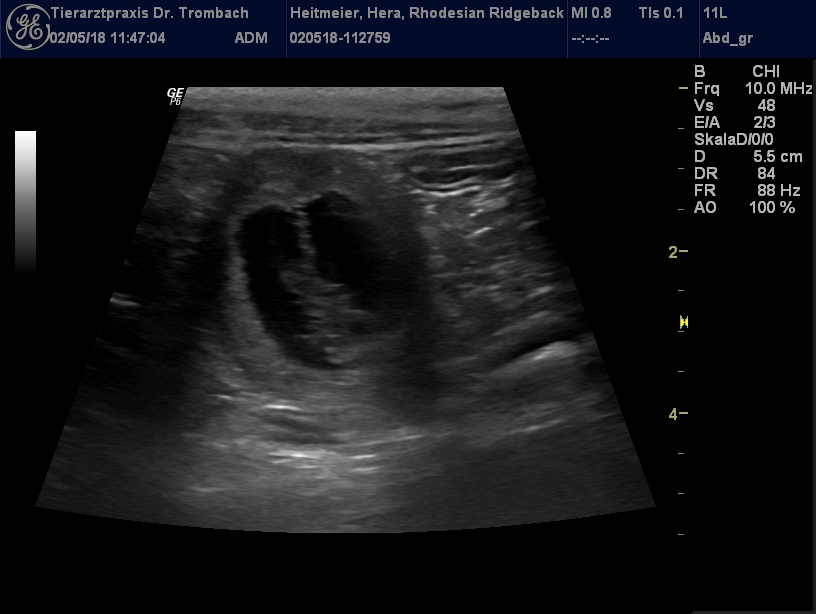

Der Ultraschall vom 02.05.2018 brachte freudige Gewissheit